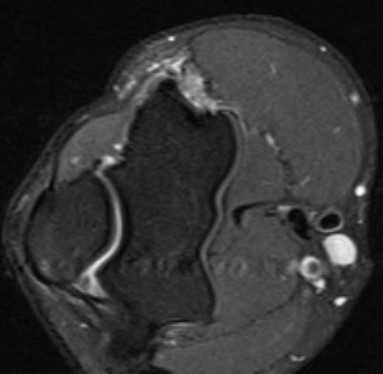

МРТ локтевого сустава в аксиальной проекции в норме

На рисунке в аксиальной проекции показана надмыщелковая область плеча. В венечной ямке и ямке локтевого отростка можно увидеть переднее и заднее жировые тела соответственно. Плечевая мышца расположена в переднем компартменте дистального отдела плеча. Рисунок надмыщелковой области плеча в аксиальной проекции. Трехглавая мышца истончается и продолжается в сухожилие, прикрепляющееся к локтевому отростку. Локтевой нерв и задняя возвратная локтевая артерия удерживаются в локтевом канале с помощью дугообразной связки (фасции Осборна). Рисунок в аксиальной проекции (непосредственно ниже локтевого сустава). Общее сухожилие разгибателей лежит над лучевой коллатеральной связкой и плохо различимо на этом уровне. Локтевой нерв покинул локтевой канал и прободает локтевой сгибатель запястья. Рисунок на уровне проксимального лучелоктевого сустава в аксиальной проекции. Хорошо различимы суставные поверхности проксимального лучелоктевого сустава, так как головка лучевой кости удерживается в лучевой вырезке локтевой кости кольцевидной связкой. Латеральная лучевая коллатеральная связка срастается с задним отделом кольцевидной связки. Рисунок локтевого сустава в аксиальной проекции непосредственно выше бугристости лучевой кости. Сухожилие плечевой мышцы прикрепляется к локтевой бугристости, а сухожилие двуглавой мышцы приближается к месту своего прикрепления к бугристости лучевой кости, расположенной дистальнее, чем место прикрепления плечевой мышцы. На уровне проксимального отдела предплечья мышцы начинают распределяться в передний компартмент (сгибатели) и задний компартмент (разгибатели).